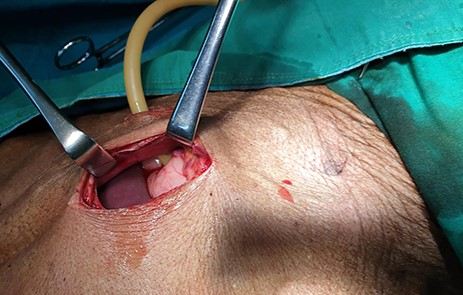

The patient was scheduled for GFT insertion, whereby a 24Fr urinary catheter was inserted via the paramedian incision into the stomach and secured using the Stamm technique (Fig. 2). Intraoperatively the liver had no lesions. The patient was sent to the general ward and semi-solid feeds were initiated through the gastrostomy feeding tube. The patient was discharged on the second day and was instructed to continue with semi-solid feeds, and wound dressing at a nearby health centre. The care-taker was clearly instructed to spigot the catheter after use and to flush the food contents with water after every meal to avoid blockage.

Patient was scheduled for GFT insertion, blood transfusion and hematemics were given and control haemoglobin obtained was 13.4 g/dl. Surgery was done and the findings were a collapsed stomach and a non-nodulated liver, a 24Fr urinary catheter was inserted, ballooned and secured using the Stamm technique (Fig. 5). Patient was transferred to the general ward and was discharged on the second day post-surgery.

The patient was scheduled for GFT insertion. Under aseptic technique, with the patient in supine position, 24 Fr urinary catheter as an improvised GFT was inserted in Stamm manner, haemostasis achieved, abdomen closed in layers and dressed (Fig. 9). There was no ascites and mesenteric lymph nodes were not palpable. After the procedure the patient was discharged home on the second day with analgesics and was booked for a surgical outpatient clinic appointment after 2 weeks.

24Fr urinary catheter as an improvised gastrostomy feeding tube.